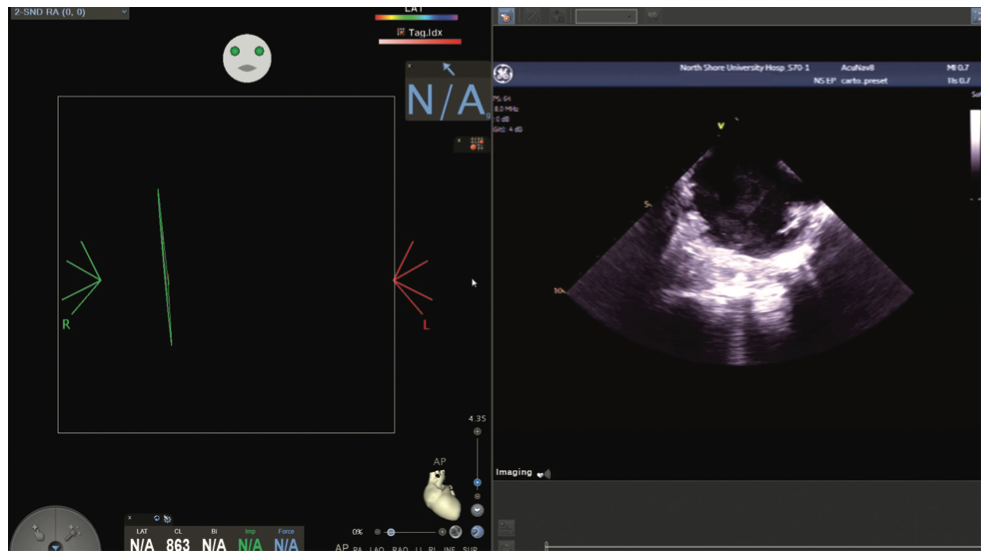

Figures/Videos 1-10 demonstrate the process of navigation from groin access to the heart to create biatrial geometry, localize the esophagus, and gain transseptal access. Many currently practicing electrophysiologists use very little fluoroscopy to map and ablate the left atrium (LA) with the current multielectrode catheters and EAM systems once transseptal access is obtained.